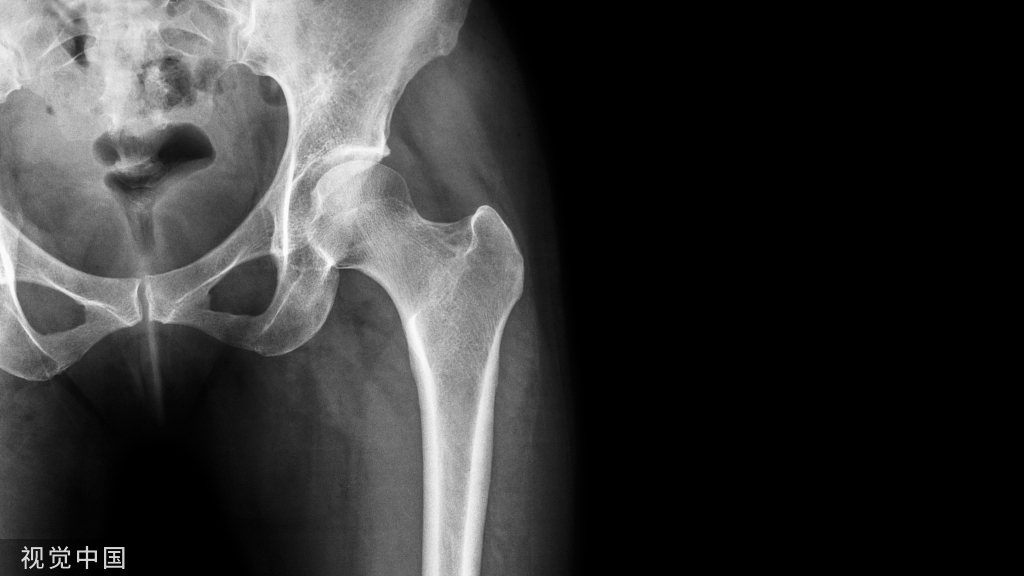

影像学资料

使用多孔钽假体(左髋关节)重建Paprosky IIB缺损的X线片:a)术前和b)术后10年的正位X线片。